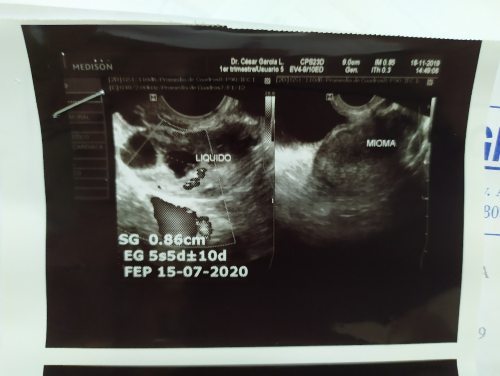

Se indican estudios de laboratorio: ante la sospecha clínica de embarazo se solicita β-HCG cualitativa la cual resulta positiva y cuantitativa que reporta resultado de 323 UI/L, grupo sanguíneo O Rh (+). Se realiza ecografía transvaginal (Figuras 1,1; 1,2; 1,3) que reporta útero en anteversión de contornos regulares, diámetros 7,7 x 5,2 x 6,2cm con un volumen estimado de 132cc, la ecogenicidad de su miometrio está afectada por una lesión hiperecogénica en relación a mioma que mide 1,9 cm en pared anterior, ovario derecho aumentado de volumen doloroso a la exploración de 4,2 x 2,2cm con imagen de pseudo saco con líquido en su interior y una imagen folicular de 1 cm en el mismo anexo, ovario izquierdo normal, espacio de Douglas luce libre; lo cual sugiere embarazo ectópico accidentado de ovario derecho.